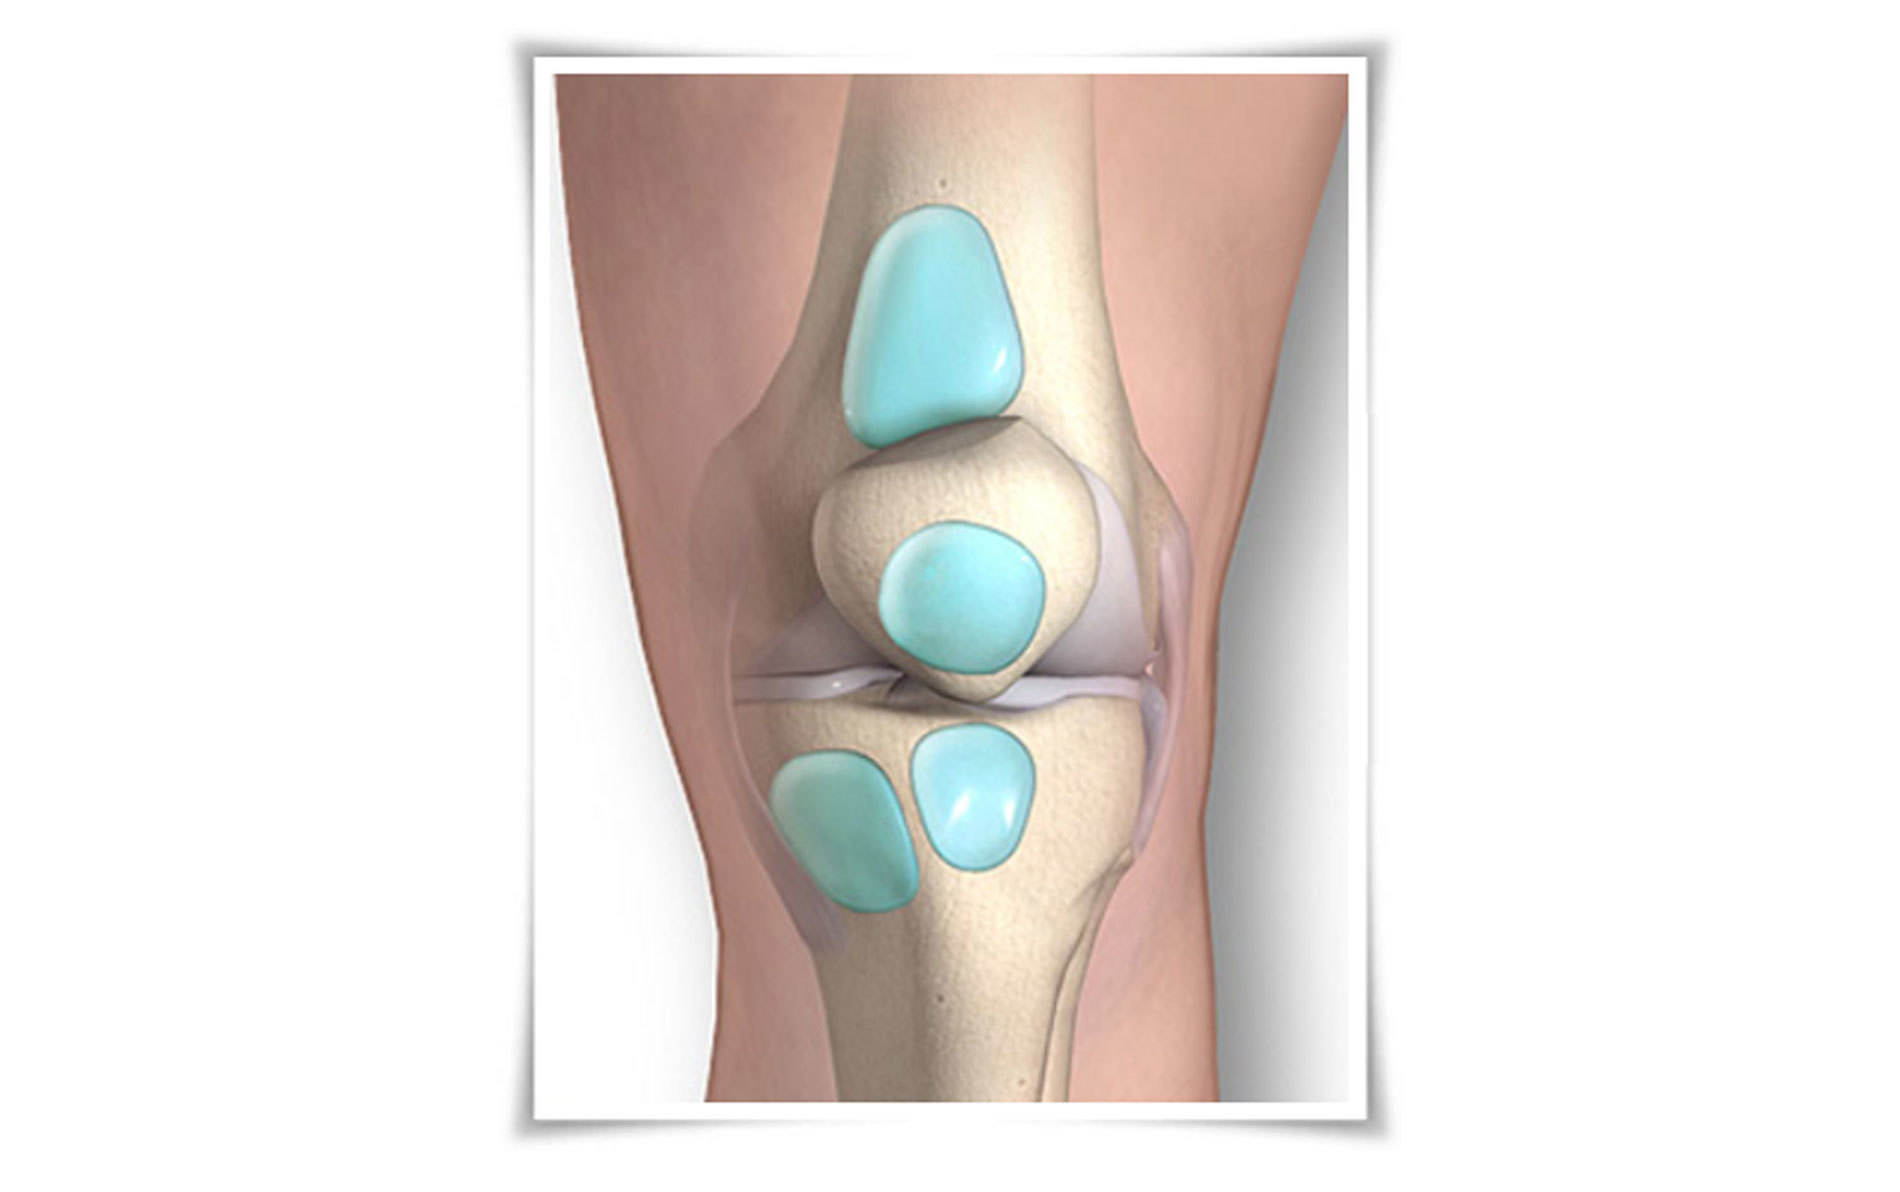

60세 이상의 환자에서  흔히 발생하는 퇴행성 질환으로 서있거나 걷는 등의 체중부하 운동에 의하여 악화되고 휴식 시 완화되는 양상을 보입니다. 아침에 일어나면 경직을 느끼고 활동하면서 풀리기도 합니다.

운동범위가 감소하고 관절의 부종, 마찰음이 관찰되기도 합니다.

주사치료 시 사용되는 연골주사는 관절의 윤활작용과 점성을 회복시켜 통증을 줄이고 기능을 향상 시킵니다.

스테로이드 주사는 염증 감소 효과는 뛰어나지만 일시적이며 장기간 사용시 오히려 관절염의 악화를 불러옵니다.

주사와 보전적 치료에도 증상이 심할 경우 인공관절치환술을 고려합니다.